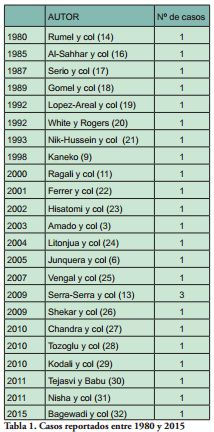

Los odontomas erupcionados son lesiones poco usuales, y el primer caso fue reportado en 1980 por Rumel y col (14). En la revisión de la literatura de Junquera y col., 2005 (6) se cita un promedio de edad de 20,3 años, con un rango de 9 a 59, situados la mayoría en maxilar superior y del tipo complejo. Serra Serra y col., 2009 (13) presentan una revisión de 20 casos de odontoma de erupción, con una edad promedio de 25,3, predominancia de género femenino y mayoría de odontomas del tipo complejo.

En nuestra revisión de la bibliografía realizada en PubMed entre los años 1980 y 2015, se reportan 33 casos de odontomas de erupción (Tabla 1).

A pesar de que en los artículos revisados (Tabla 1) no se reportan todos los datos clínico-patológicos, se constata que el 59, 25 % de los odontomas de erupción se localizan en la mandíbula, con rangos etarios que se sitúan entre 8 y 27, con un promedio de 17,6 años, sin diferencia significativa de género. Del punto de vista histológico los odontomas complejos son los más frecuentes, representando el 42,4 % de los odontomas de erupción.